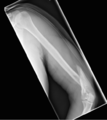

A transverse fracture of the humerus shaft

A spiral fracture of the humerus shaft